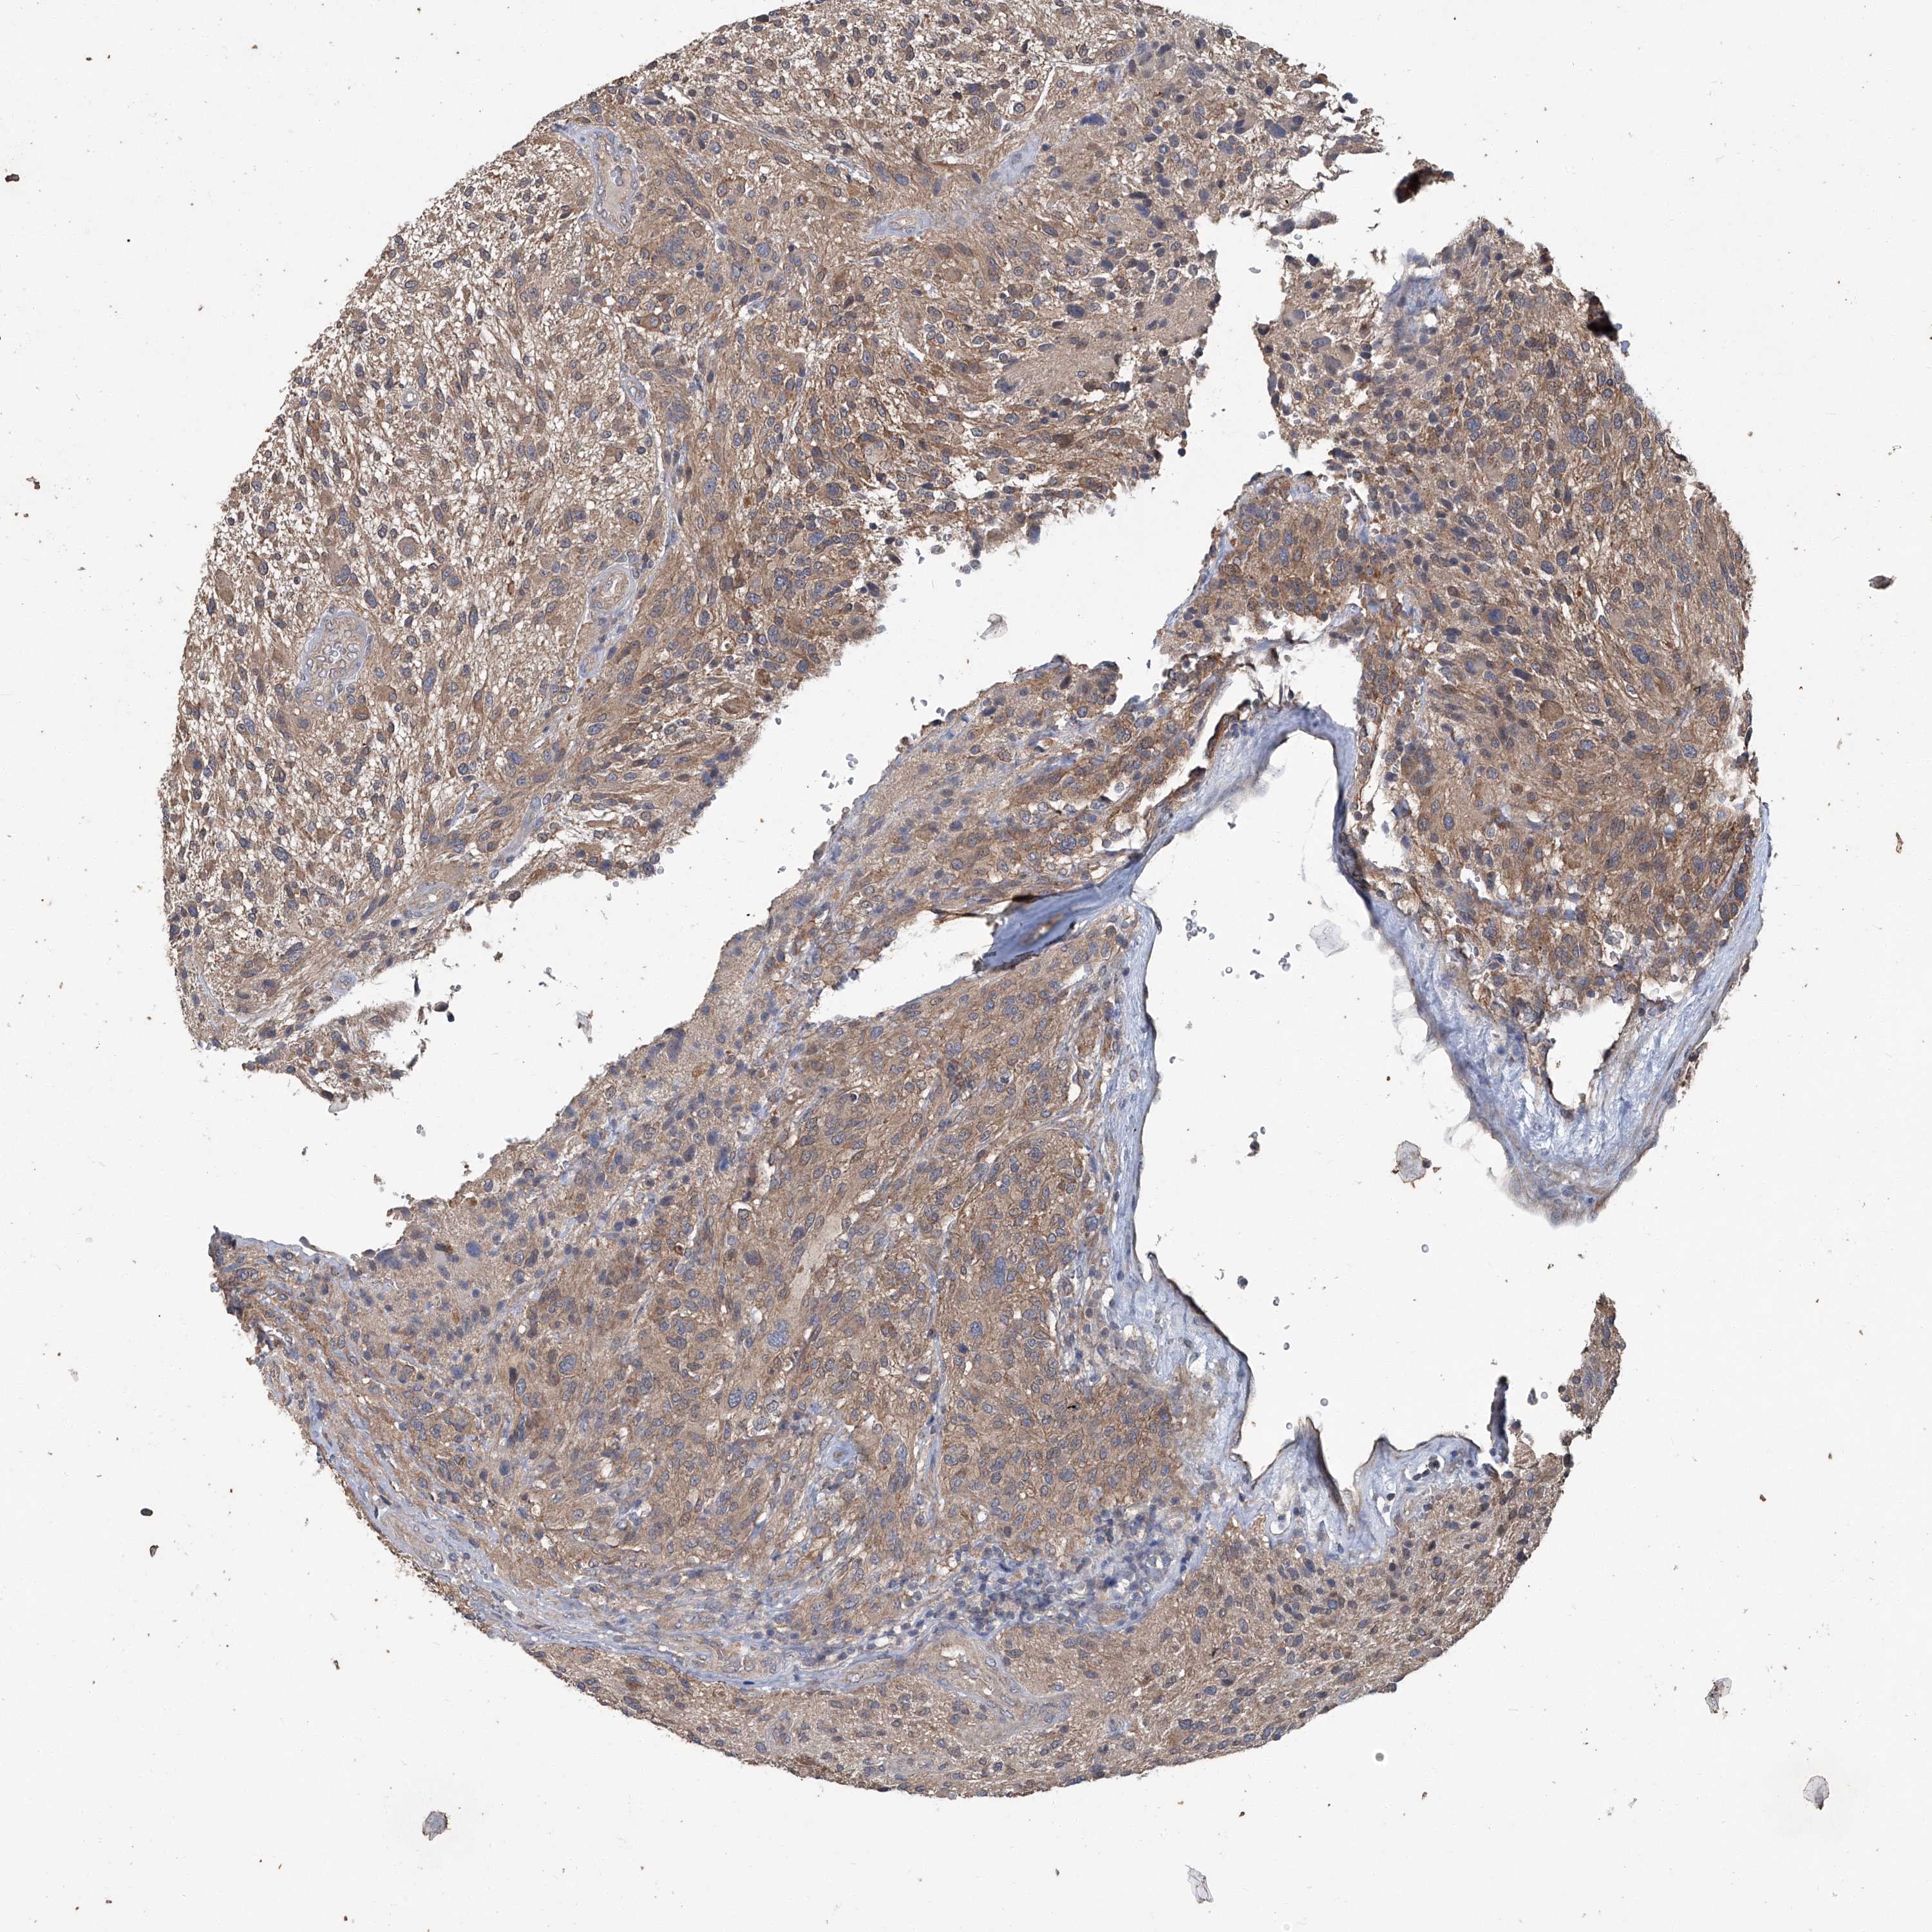

GLIOMA - Protein expressioni

A mouse-over function shows sample information and annotation data. Click on an image to view it in a full screen mode. Samples can be filtered based on level of antibody staining by selecting one or several of the following categories: high, medium, low and not detected. The assay and annotation is described here.

Note that samples used for immunohistochemistry by the Human Protein Atlas do not correspond to samples in the TCGA dataset.

Antibody stainingi

Antibody staining in the annotated cell types in the current human tissue is reported as not detected, low, medium, or high, based on conventional immunohistochemistry profiling in selected tissues. This score is based on the combination of the staining intensity and fraction of stained cells.

Each image is clickable and will lead to virtual microscopy that enables deeper exploration of all samples and also displays staining intensity scores, fraction scores and subcellular localization as well as patient and tissue information for each sample.

Antibody HPA029642

Antibody HPA029643

Glioma, malignant, Low grade

Glioma, malignant, High grade

Glioblastoma, NOS